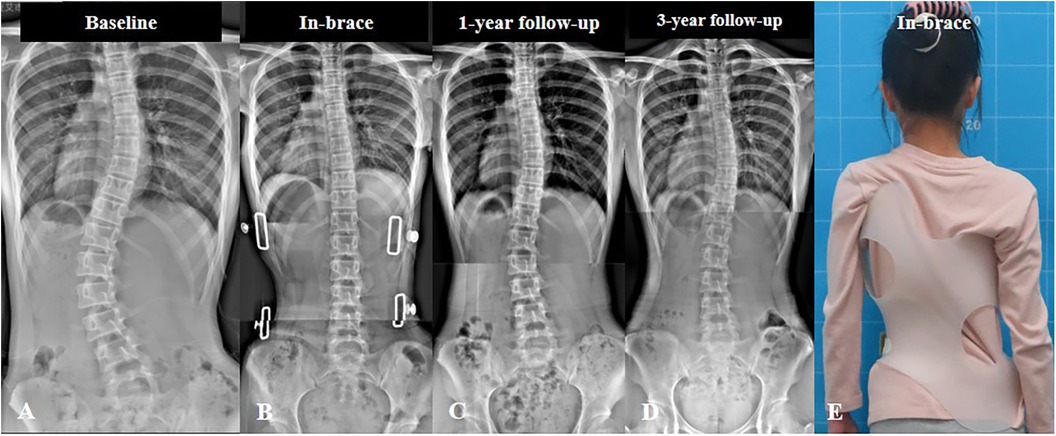

كيف تؤثر عدد انحناءات اعوجاج العمود الفقري على خطة العلاج؟

عدد الانحناءات يؤثر مباشرة على:

عدد ساعات ارتداء الحزام

مدة العلاج والمتابعة

قرار التدخل الجراحي في الحالات المتقدمة

على سبيل المثال، الطفل الذي لديه انحناء واحد بسيط قد يحتاج فقط إلى متابعة وتمارين، بينما الطفل الذي لديه انحناءان قد يحتاج إلى حزام مصمم بدقة أكبر.

هل يمكن أن يتحول الانحناء الواحد إلى أكثر من انحناء؟

نعم، في بعض الحالات ومع النمو السريع، قد يظهر انحناء تعويضي جديد إذا لم تتم المتابعة أو العلاج في الوقت المناسب.

لهذا السبب تعتبر المتابعة الدورية أمرًا أساسيًا حتى في الحالات البسيطة.

في الأطفال والمراهقين خلال فترات النمو السريع، قد تتغير شكل الانحناءات مع الوقت، سواء من حيث العدد أو الشدة.

لذلك، لا يكفي تشخيص واحد فقط، بل يجب إعادة التقييم بشكل دوري.